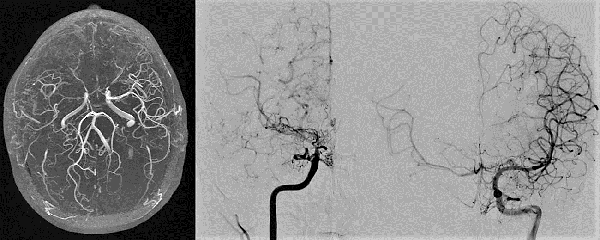

Caso clínico # 2: LD femenino de 51 años con antecedente de tabaquismo e hipertensión arterial, estudiada por deterioro cognitivo de varios meses de evolución. La RMN y ARM evidencia atrofia de hemisferio cerebral izquierdo con hiperintensidad periventricular y disminución franca del calibre de las arterias cerebral anterior y media izquierda con desarrollo de los vasos de MM (Fig. 3). La ADC muestra el stop de la arteria carótida interna izquierda distal y ausencia del origen de las cerebrales anterior y media, buen desarrollo de los vasos de MM y aporte de vasos meníngeos y etmoidales correspondiente a un grado 4 de Suzuki (Fig. 4). Se realizó una revascularización cerebral combinada: un bpTS izquierdo más EDMS y, para aumentar la perfusión en territorio de ambas arterias cerebrales anteriores, un EGPS bifrontal. En la TAC postoperatoria se evidenció un infarto fronto-polar mesial sin repercusión clínica. La ADC postoperatoria diferida evidencia una buena revascularización en los territorios de las arterias cerebral anterior y media a partir del bpTS y la doble sinangiosis (Fig. 5).

Fig. 3 Caso clínico # 2. RMN y ARM preoperatoria, se evidencia atrofia de hemisferio cerebral izquierdo con hiperintensidad periventricular y disminución franca del calibre de las arterias cerebral anterior y media izquierda con desarrollo de los vasos de MM

Fig. 4 Caso clínico # 2. ADC preoperatoria con compromiso bilateral de las arterias carótidas supraclinoidea mayor a izquierda, vasos de MM y presencia de anastomosis leptomeníngeas. Nótese el signo de la botella de champagne en el origen de la arteria carótida interna cervical, presente en los MM avanzados. Corresponde a un grado 4 de Suzuki

Fig. 5 Caso clínico # 2. Postoperatorio. A la izquierda una TAC con pequeño infarto frontomesial. La imagen del centro es una ADC de frente que muestra el bpTS con muy buena perfusión cerebral. La imagen de la derecha es la ADC de perfil que muestra una buena perfusión cerebral a partir de la EGPS bifrontal